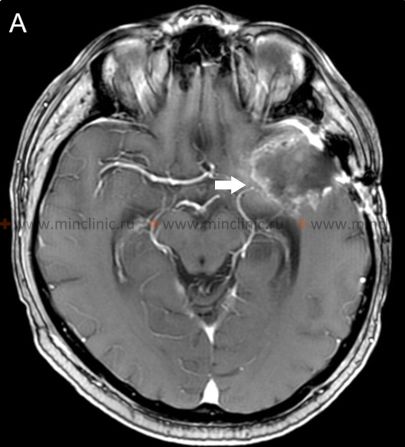

Crucially, before initiating anticoagulant therapy (blood thinners) in a patient presenting with acute stroke symptoms suggestive of cerebral embolism, it is essential to obtain urgent brain imaging, typically a non-contrast computed tomography (CT) scan [16]. The primary purpose of this initial scan is to reliably exclude the presence of intracranial hemorrhage (bleeding), as anticoagulants are contraindicated in hemorrhagic stroke and could worsen bleeding [16]. While CT is excellent for detecting acute blood, magnetic resonance imaging (MRI) is more sensitive for detecting early ischemic changes and differentiating acute from chronic hemorrhage or prior infarcts [14, 16].

A lumbar puncture (spinal tap) to examine the cerebrospinal fluid (CSF) for red blood cells is generally *not* indicated in the routine evaluation of suspected embolic stroke [1]. Its utility is very limited, primarily considered only in rare situations where subarachnoid hemorrhage is strongly suspected but initial CT scans are negative or equivocal, or perhaps historically when advanced imaging was unavailable and differentiating small brainstem hemorrhages (e.g., pontine) from infarcts was difficult [1]. Bone artifacts on CT scans, particularly in the posterior fossa (brainstem and cerebellum), can sometimes obscure small hemorrhages [14]. Modern magnetic resonance imaging (MRI), especially sequences sensitive to blood products (like gradient echo or susceptibility-weighted imaging), is far superior for differentiating acute from chronic hemorrhage and is highly sensitive for detecting early ischemic changes (infarction) within hours of onset [14, 16].

If cerebral artery embolism is suspected, identifying the location of the arterial occlusion and assessing the downstream brain tissue is critical for guiding acute treatment (like thrombectomy) [16, 19]. Non-invasive vascular imaging, such as CT angiography (CTA) or MR angiography (MRA), is typically performed urgently [16]. Conventional catheter-based cerebral angiography (Digital Subtraction Angiography - DSA) provides the highest resolution detail of the vessels but is invasive [14]. It may be performed if endovascular treatment (thrombectomy) is planned or if non-invasive imaging is inconclusive [16, 19]. It's important to note that after several hours or days, an embolus might migrate distally, fragment, or undergo spontaneous lysis (dissolution), meaning that angiography performed later might not show the original occlusion, making the definitive diagnosis of embolic stroke sometimes presumptive based on clinical presentation and infarct pattern [1]. Standard intravenous contrast administration during a routine CT or MRI scan generally lacks the resolution and timing necessary to directly visualize small cerebral emboli within vessels [14].